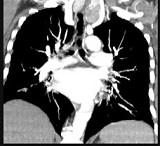

问题 40岁,女,发现颈部肿块,随吞咽上下移动,触之无搏动,咳嗽、气喘一周,请结合CT检查选择最可能的诊断()

选项 A.胸腺瘤 B.胸内甲状腺瘤 C.无名动脉瘤 D.无名动脉伸展扭曲 E.淋巴瘤

答案 B